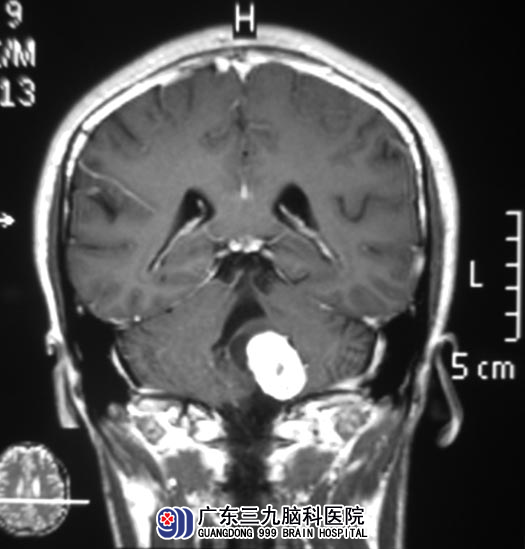

他的父亲不敢马虎,在当地医院给小区行头颅CT检查,结果提示:左侧桥小脑角区占位。广东三九脑科医院头颅MR检查提示:病灶大小约29.7mm×21.1mm×28.5mm,脑桥左侧受压变形。

完善相关检查后,由综合神经外科 鲁明主任主刀,在全麻下行左侧桥小脑角区肿瘤切除术,术中显微镜下见肿瘤位于左侧桥小脑角,临近延髓,肿瘤呈灰白色,质韧,仔细分离肿瘤粘连动脉及静脉,术中对后组颅神经保留完整,肿瘤顺利全切。术后小区未出现后组颅神经损害症状,康复出院。病理结果为:神经鞘膜瘤。